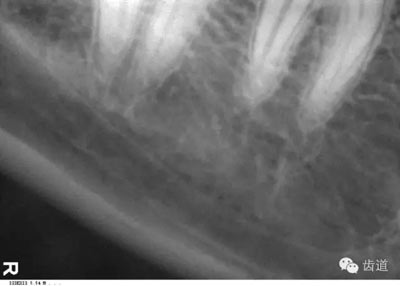

位于磨牙牙根尖下方,呈寬約為0.4cm凹面向下邊緣整齊的帶狀密度低的影像,其兩側(cè)有密度高的線條狀影像,為下頜管骨密質(zhì)

膠片在口內(nèi)放的位置過(guò)低,在牙根尖下方X線片上顯示為帶狀密度很高的影像。